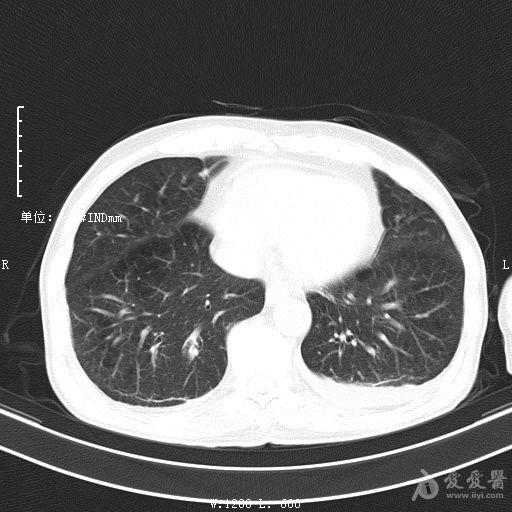

最新的肺炎疫情形勢嚴(yán)峻,病毒變異使得防控工作更加復(fù)雜,許多地方出現(xiàn)了新的病例,甚至有些地區(qū)的疫情出現(xiàn)了反彈,這不僅是對醫(yī)療系統(tǒng)的考驗(yàn),更是對每一個(gè)生命的考驗(yàn),我們需要密切關(guān)注疫情動態(tài),共同應(yīng)對這場挑戰(zhàn)。??